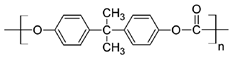

| Polymers | Structure | Fabrication Method | Commercial Products/Literatures | Comments | Reference |

|---|---|---|---|---|---|

| Polycarbonate (PC) |  | Ion-track etching | Estrogen | Excellent stability against oxidation and biodegradation and improves antifouling properties | [151] |

| Polyethylene (PE) |  | Ion-track etching | Catapress (Clonidine), Boehringer IngelheimClimara (Estradiol), Berlex | Physico-chemical stability andordered pore formation with superior membrane performance | [152] |

| Polyethylene terephthalate (PET) |  | Lithography | Ketoprofen | Biostable, antifouling, has better performance of membranes, in useful in preparing surgical meshes and ligaments | [153] |

| Polystyrene (PS) |  | Lithography | d-limonene, ibuprofen | Chemical resistance, easy processing, lower cost, exhibits enhancements in strength, stiffness, toughness, and ductility | [154] |

| PC, PE | - | Ion-track etching | Estraderm (Nitroglycerin), Rotta Research | Cost-effective and biocompatibility is fairly good | [155] |

| PC, PE, PET, PS | - | Phase separation | Deponit (Nitroglycerin), Pharma SchwarzHabitrol (Nicotine), Novartis | Cost-effective and biocompatibility is fairly good | [154,156] |

| Polyurethane (PU) |  | Sol-gel/solvent casting | Vivelle (Estradiol), Novartis | Good elasticity, biodegradable, suitable for hydrophilic drugs, biocompatibility is fairly good | [154] |

| Polysiloxane (silicone) |  | Sol-gel/solvent casting | Prostep (Nicotine), Lederle, Transderm Nitro (Nitroglycerin), AlzaSyncro-Mate-C (Norgestomet) | Better insulation, excellent biocompatibility, and fabricated easily for hydrophilic drugs | [157] |

| Polyisobutylene (PIB) |  | Solvent casting | Aminopyrene, Mitsubishi Petrochem Co., Japan | Good adhesive drug impermeable layer and high degree of tack or self-adhesion | [158] |

| Polymethyl methacrylate (PMMA), poly (2-hydroxy ethyl methacrylate) |  | Layer by layer deposition | Androderm (Testosterone), SmithKline Beecham | Physical strength and transparency | [159] |

| Polyvinyl alcohol (PVA), Poly (ethylene-co-vinyl acetate) |  | Solvent casting | Nitro-Dur I (Nitroglycerin), Key PharmaTestoderm TTS (Testosterone), Alza | Rate-controlling membranes, high membrane permeability, hydrophilicity and strength, suitable for lipophilic drugs | [160] |

| Polyacrylic acid, polyacrylate, polyacrylamide |  | Layer by layer deposition | Epinitril (Nitroglycerin), Rotta ResearchMonsanto (Fentanyl), Dow Corning | Good adhesivity and spreadability and contains a drug impermeable layer | [160] |

| Polylactides (PLA), polylactic-co-glycolic acid (PLGA), polyglycolides (PGA) |  , ,  | Sol-gel/solvent casting | Propranalol, Exxon Chemical Co. | Good biocompatibility; lactic and glycolic acids are the degradation products and they are easily eliminated from the body | [161,162] |

| Polyvinyl pyrrolidone (PVP), poly (N-vinyl pyrrolidone) |  | Sol-gel/solvent casting | Cytarabine, ara-ADA, Polyscience | Superior biocompatibility, has suspension capabilities, antinucleating agent, and enhances release rate | [163] |

| Polyethylene glycol (PEG) | Sol-gel/solvent casting | Miconozale, Rohm, Germany | Chemically inert and free of leachable impurities | [164] | |